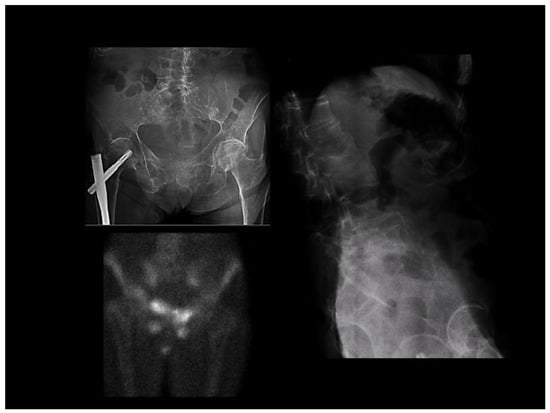

- OM phase: in this phase, signs are observed in the imaging tests, which are added to the previous clinical picture.

| (a) Hypophosphatemia or hypocalcemia; (b) Elevated bone alkaline phosphatase; (c) Muscle weakness or bone pain; (d) BMD <80% in young adults; (e) Image: multiple uptake bone zones or Looser–Milkman fractures. |

| The above criteria, applied in the absence of kidney or liver disease, suggest the diagnosis of OM. The additional presence of symptoms and Looser zones helps in advanced phases. |